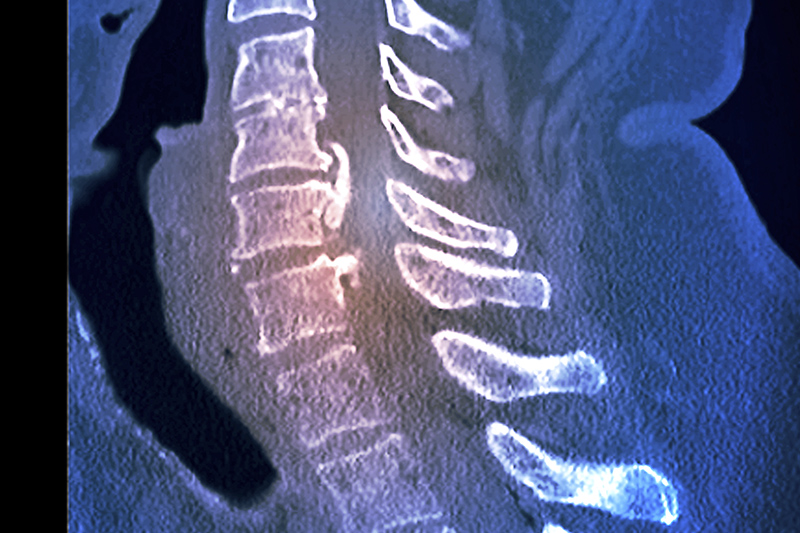

6000iCT (필립스) CT(256ch)

- - 저선량 디지털 detector 탑재 → 혁신적인 심장.뇌 촬영효과

- 진단의 정확도 극대화(AI 플래닝 알고리즘 탑재)

- 안전한 촬영 → 초 저선량으로 최적의 이미지 획득 가능

- 고화질 영상 제공-노이즈 제로영상